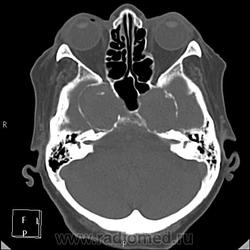

Да простят моё нахальство уважаемые специалисты КТ. Я вижу тут огромные инкапсулированные узлы расположенные почти симметрично справа и слева от турецкого седла, которое разрушено узлом поменьше. Латеральные злы продавливают дно средней черепной ямы. По-видимому, здесь доброкачественная опухоль типа «аденома», исходящая из гипофиза и давно растущая. Обызвествление есть не только в капсулах узлов, но и в их толще (очаговое). При таких размерах узлов и косных разрушениях, нет сомнения, пострадали и зрительные нервы.

Цифровых и плёночных доказательств на руках нет. Опухоль диагностирована в 2004 году, размером "с вишню", дебютировала птозом века правого глаза, умеренной головной болью в лобной области слева и постепенным снижением зрения, катаракта. Пациентка с трезвом уме и превосходной памяти (на мой субъективный взгляд))). В выписке результаты КТ, МРТ: неоперабельная опухоль селлярно-параселлярной области с прорастанием кавернозных синусов, аневризма сифона внутренних сонных артерий. Цитологию НЕ брали.

Насчет опухоли у меня большие сомнения. То что седло растянуто, еще не показатель. Седло увеличивается в размерах даже при гипертонии,а тут такие аневризмы. Самой опухоли не видно, в просвете турецкого седла медиальные полюса аневризм. Ну впрочем не так это важно, интерес чисто теоретический, да и верификации видимо не будет. Спасибо большое за демонстрацию.